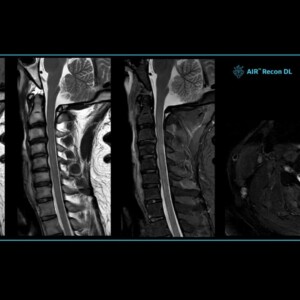

Σε αυτή την εξέταση απεικονίζεται με τη χρήση ή χωρίς σκιαγραφικού μέσου το παρέγχυμα ,τα οστά και όλες οι δομές του εγκεφάλου των νεύρων και του νωτιαίου μυελού διαγιγνώσκοντας παθήσεις όπως υδροκεφαλία, ριζίτιδες, όγκους κ.α.

Χρησιμοποιώντας τους υπερσύγχρονους μαγνητικούς τομογράφους μας καθίσταται δυνατή η ακριβής απεικόνιση (σε διατομές και 3D) των αγγείων του σώματος αορτή, εγκεφάλου, μηριαίων κ.α, τον έλεγχο ροής του αίματος σε αυτά με σκοπό την διάγνωση ανευρυσμάτων, στενώσεων και άλλων παθολογιών.